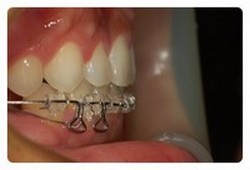

맞다 저 브라켓 탈락 상습범이엇던거 아시죠 ㅠㅠ

진짜 신기한건 저렇게 양옆으로 붙인뒤로는 단한번도 안떨어지는중 ~~~

이젠 브라켓 탈락 걱정없이 더욱더 잘 먹고 잇습니다 ㅋㅋ